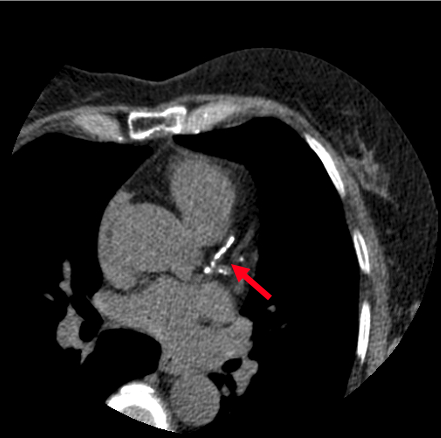

Coronary Calcium Scan

The presence of calcium deposits in the coronary arteries means that plaque is starting to build up. Over time, plaque can rupture and cause a blood clot to form, further blocking the blood and oxygen supply to the heart. These blocked coronary arteries raise the risk of a heart attack.

buildup of calcium in the heart